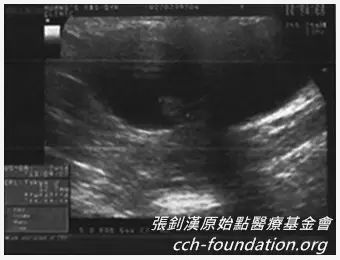

后来医生证实我们

这个过程是流得非常的干净

这才完全放心